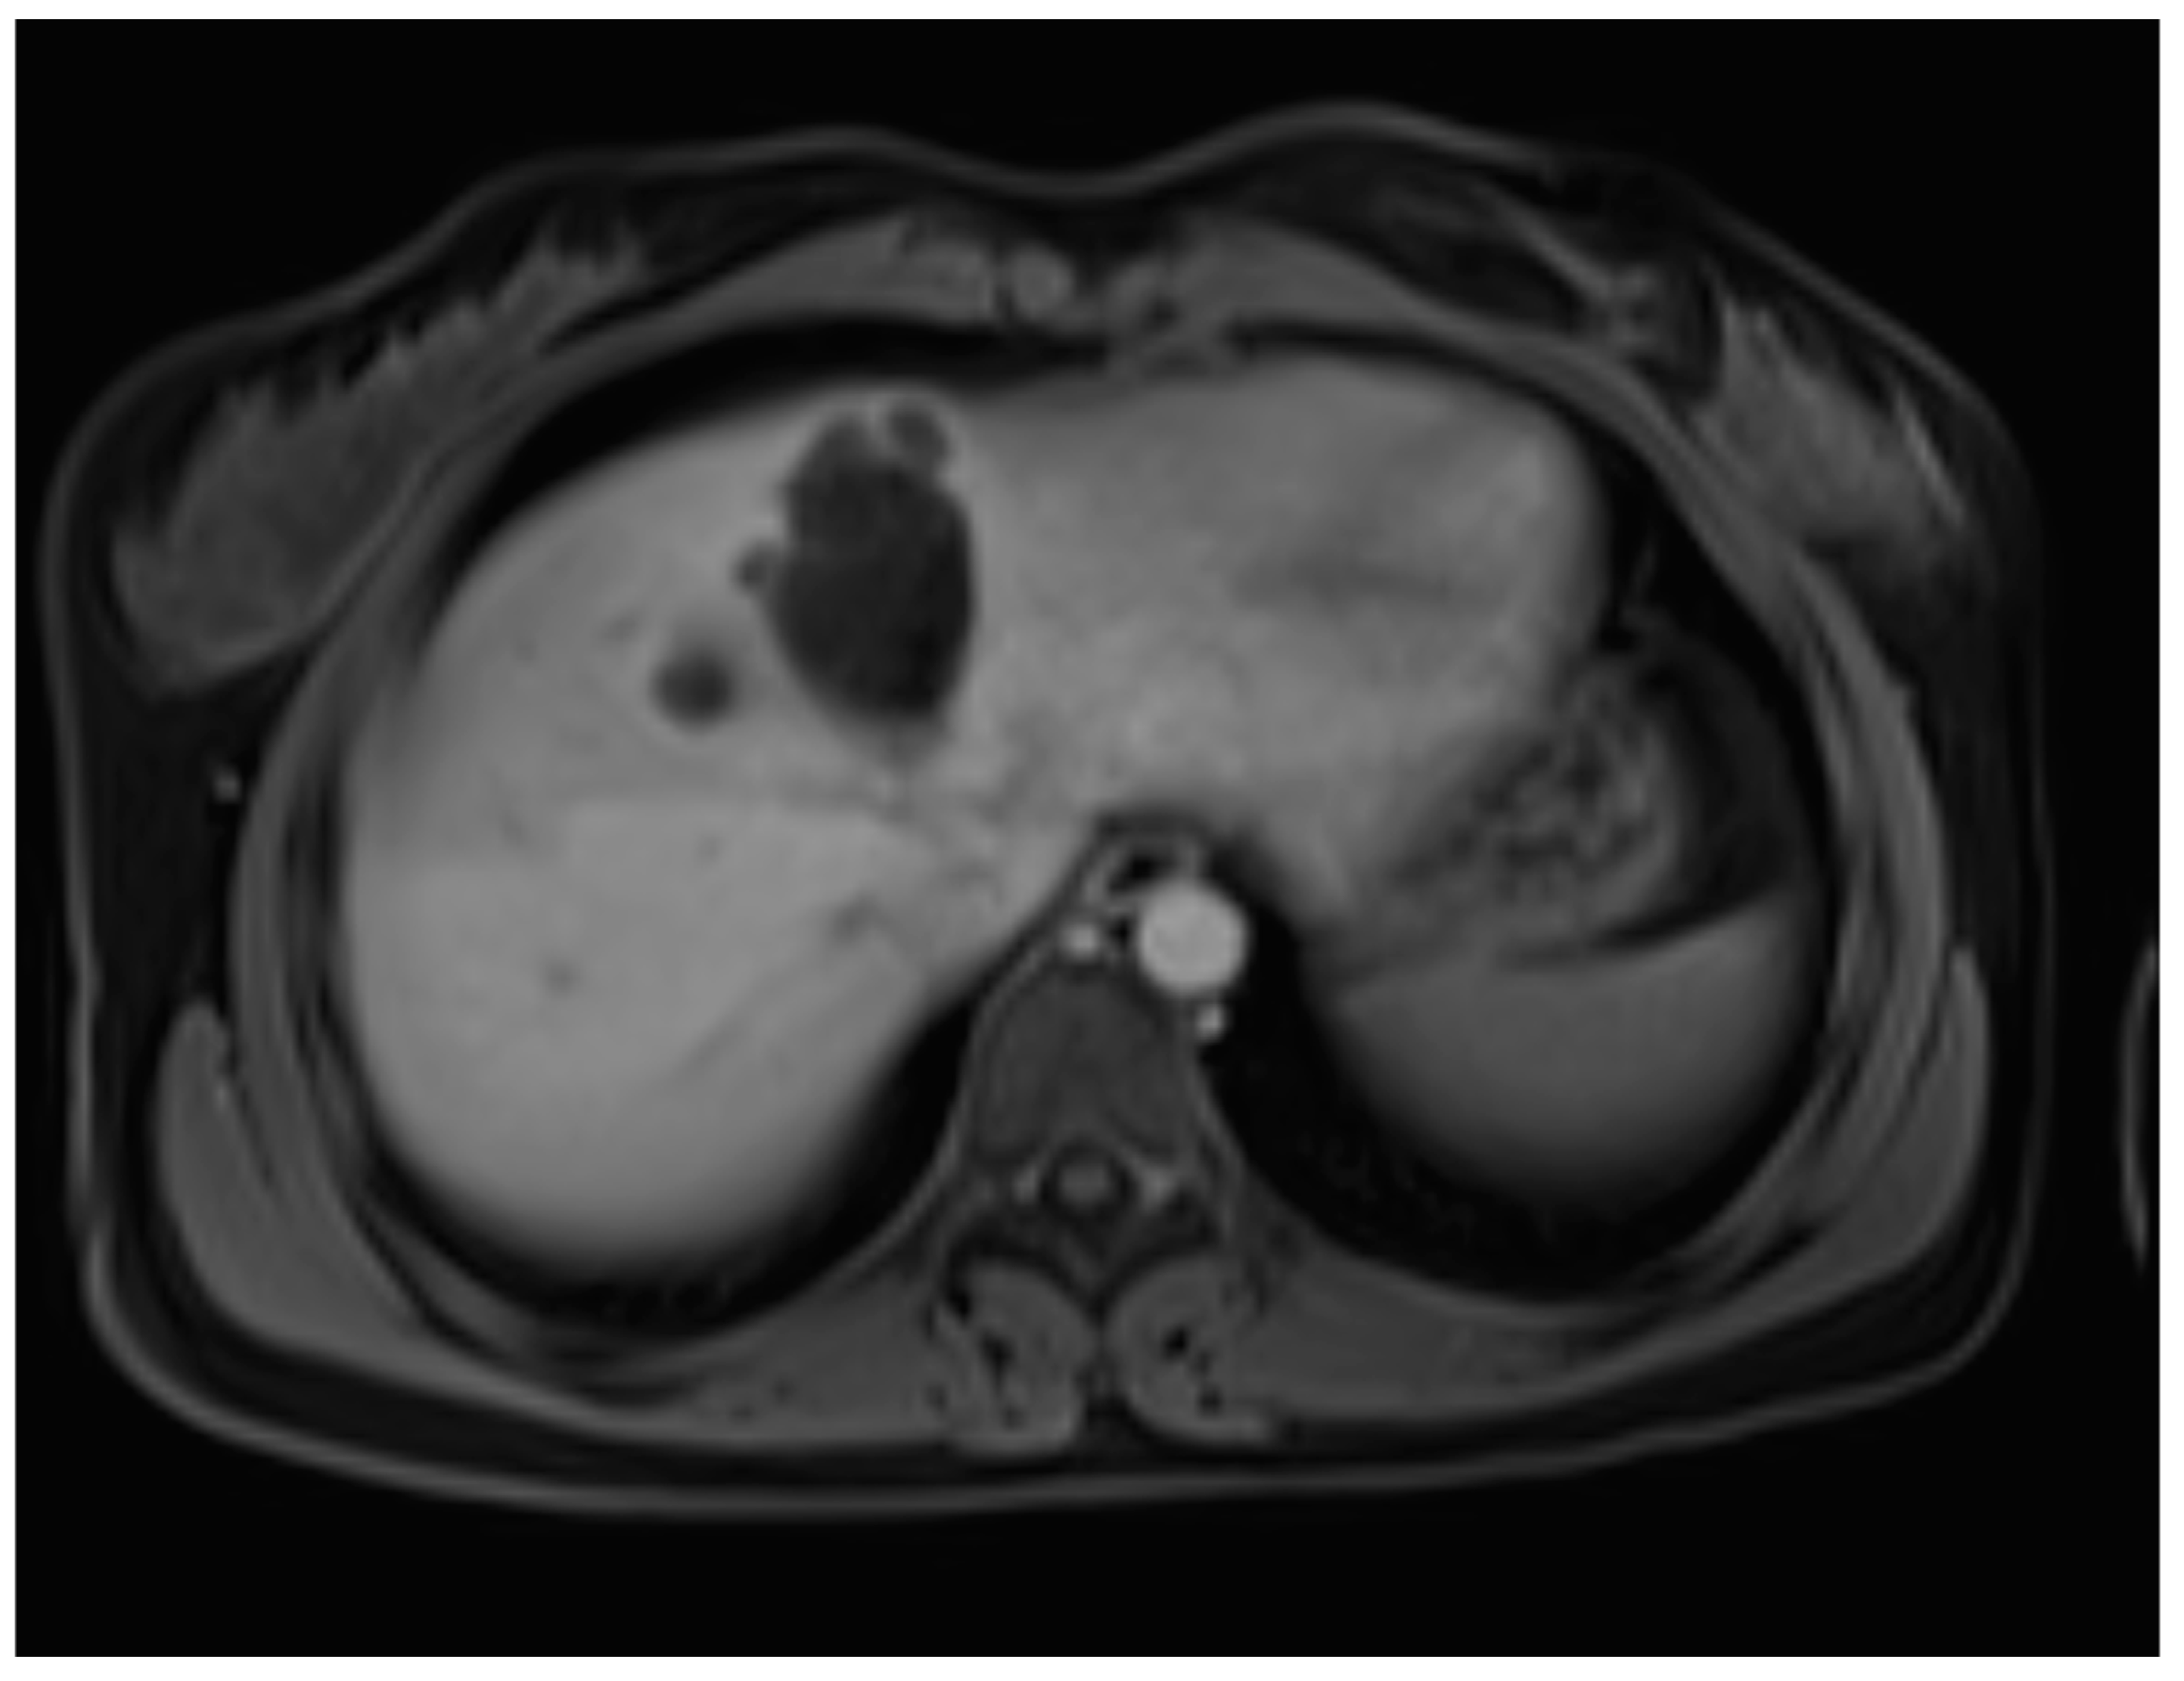

A liver MRI scan confirmed a cystic structure with multiple daughter cysts, hypointense on a T1-weighted image (T1WI), and hyperintense on a T2-weighted image (T2WI), with no solid components, no signs of membrane rupture, and a maximum diameter of 10 cm (craniocaudal) (Figure 1). Additionally, elevated signals on T2WI in the surrounding liver tissue were found. The T1 sequences did not reveal any contrast uptake after 5 (Figure 2), 10, or 20 (Figure 3) minutes post-injection. Furthermore, DWI/ADC mapping indicated a hydatid cyst. The DWI sequences included a trace DWI (Figure 4), an ADC map (Figure 5), and both at b800. Radiomics and AI tools were not involved. The trace DWI showed an area of hypointensity in the region of the cyst that was surrounded by a hypointense layer, depicting the cystic wall. The ADC map revealed hyperintensity within the area, in concordance with a typical depiction of cysts on an MRI scan.

Figure 2.

First MRI scan: Axial T1W MRI scan showing hypointense daughter cysts in liver segment IV with no contrast uptake after 5 min.

In diagnosing CE, MRI scanning is of more value than CT [16]. On an MRI scan, hepatic cysts show homogeneous very-low signal intensity on T1WI and homogeneous very-high signal intensity on T2WI. Due to its fluid content, there is a notable increase in signal intensity on heavily T2WI, which helps to differentiate these cysts from metastatic lesions [17]. No enhancement is observed after the administration of gadolinium contrast. In rare cases of intracystic hemorrhage, when blood products are mixed within the cyst, the signal intensity becomes high, and a fluid–fluid level is seen both on T1WI and T2WI [15]. These features are observed within hydatid cysts as well, although there are differences regarding their histopathological features. A hydatid cyst has three distinct layers, as follows: the outer adventitial layer formed by the host’s liver tissue (pericyst), the middle laminated layer derived from the parasite, and the inner germinal layer derived from the parasite [7,16].